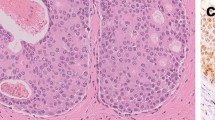

Uptake of L-methyl-11C-methionine (11C-methionine) in breast cancer metastases was studied with positron emission tomography (PET). Eight patients with soft tissue metastases were studied twice: before the onset of chemotherapy (4), hormonal therapy (3) or radiotherapy (1) and 3-14 weeks later. The radioactivity concentration of the low molecular weight fraction of venous plasma samples separated by fast gel filtration was used as input function. The input corrected uptake rate of 11C-methionine (Ki) in breast cancer metastases before the treatment ranged between 0.035 and 0.186 1 min-1 and the standardised uptake value (SUV) between 2.0 and 11.4. The uptake of 11C-methionine into the metastases decreased when clinical objective stability or regression of the metastases was later obtained and increased in cases where progressive disease was seen during treatment. We conclude that metabolic changes in the amino acid metabolism detected by PET precede the clinical response, and may be of clinical value in predicting the treatment response.